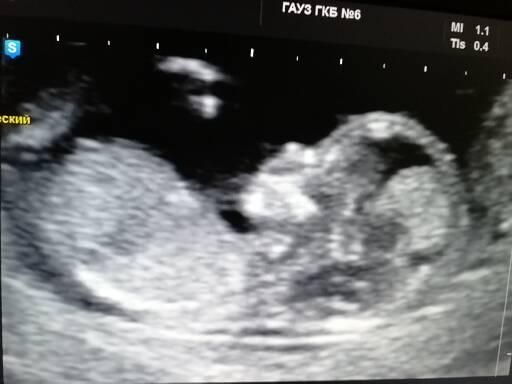

БеременностьВ ЖК доктор напутала мне срок и ушла в отпуск, поэтому я сделала платное УЗИ, чтобы просто узнать реальный срок. И, как я и ожидала, мне сообщили, что скрининг делать уже прям пора. Ну, я и сделала. Хоть пол никто и не увидел, но, как бы мне ни хотелось дочку, у меня почему-то такое ощущение, что это снова сын. Я уже не помню, что девочек тоже можно рожать)) Но, честно говоря, уже особой разницы и нет. По УЗИ всё хорошо, по крови всё хорошо - и слава богу.